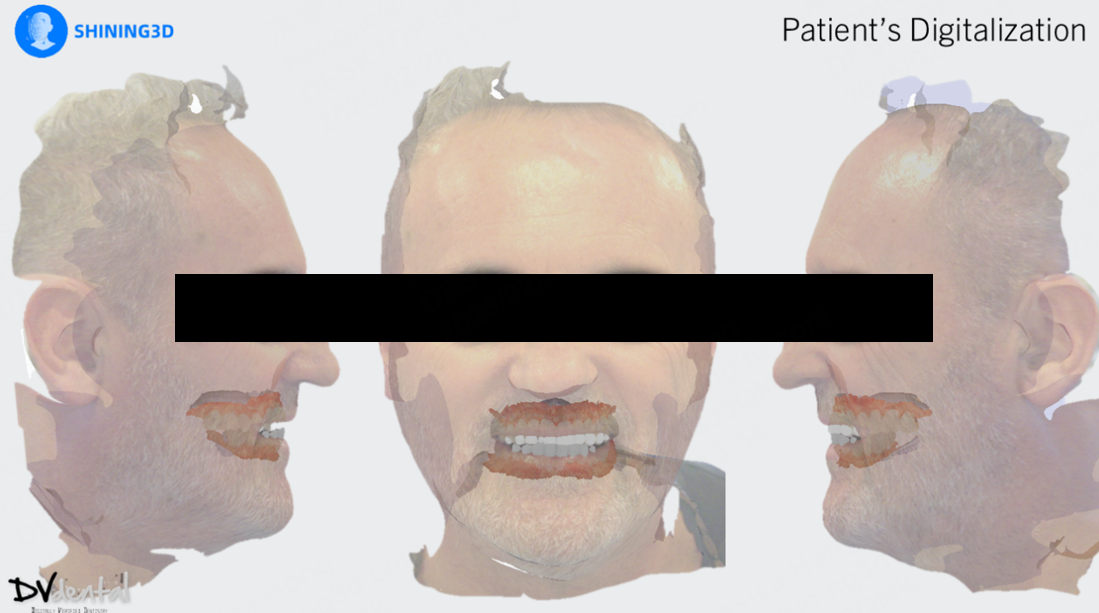

Additionally, due to the skewed smile line and unattractive appearance of the previous maxillary prosthesis, the patient expressed a desire for a more aesthetically pleasing design for the new restoration. To achieve this, we will use SHINING3D’s MetiSmile facial scanner to capture the patient’s facial data and use this data as a reference for smile design.

2. MetiSmile and acquisition of facial data

In aesthetic design, facial data can assist technicians in analyzing the patient’s facial symmetry, smile line, and the proportion of teeth to facial features, ensuring that the prosthesis harmonizes with the patient’s facial characteristics. Therefore, the application of facial scanners is crucial. The MetiSmile facial scanner from Shining 3D can capture the patient’s 3D facial data with high precision, including facial contours, lip morphology, nasolabial folds, and chin position. These data provide essential references for the aesthetic design of the prosthesis. Since both MetiSmile and Aoralscan Elite belong to the Shining 3D platform, the intraoral scan data and facial scan data can be directly matched during the facial scanning process.

After the capture process is done, we send everything to the lab. The lab mounts the data on the virtual articulator with the help of the face-scan, and designs a facially driven prosthesis for the upper jaw according to the patient’s needs. The integration of the dynamic bite within the CAD software allowed us to finalize our design functionally.